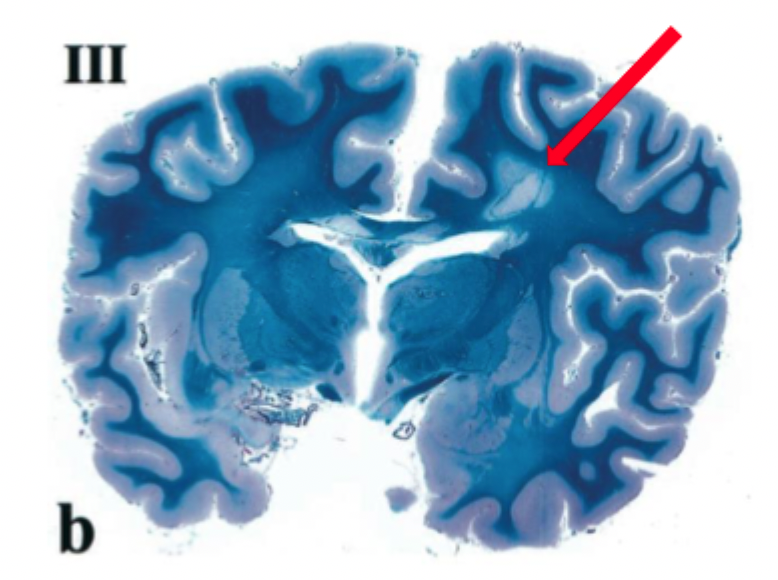

2. Hur syns detta morfologiskt i hjärnan vid t.ex. obduktionssnitt?

2. I snitt från hjärna kan man se områden som är demyeliniserade. Skoven kan ses på MR.

3. Viss remyelinisering kan ske. Men upprepade inflammationer leder till permanent demyelinisering i det drabbade området.